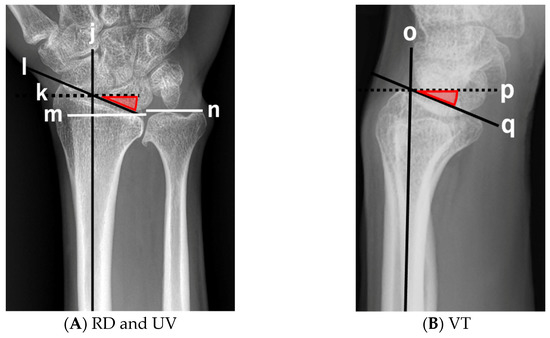

2.3.2. Wrist

| ACI | TDI | PUB | ROA | RD | VT | UV | |||

| 3 | 11 | M | 2.01 | - | 18.4 | - | 20.2 | 13.9 | −0.1 |

| 4 | 12 | F | 1.48 | 0.38 | 2.0 | 106 | 20.2 | 13.9 | 0.9 |

| 5 | 14 | M | 1.80 | 0.39 | 9.0 | 101 | 20.3 | 9.0 | −1.9 |

| 6 | 16 | F | 1.40 | 0.32 | 10.0 | 113 | 27.0 | 15.5 | 0 |

| 7 | 18 | M | 1.96 | 0.40 | 0 | 104 | 27.7 | 18.3 | −1.2 |

| 8 | 22 | M | 2.18 | 0.46 | 10.7 | 92 | 27.8 | 24.8 | 0 |

| 9 | 24 | F | 1.83 | 0.46 | 16.8 | 85 | 22.9 | 23.6 | 0.8 |

| 10 | 28 | F | 1.60 | 0.33 | 19.9 | 110 | 31.1 | 27.9 | 2.8 |

| 11 | 31 | F | 1.72 | 0.33 | 21.4 | 113 | 28.0 | 23.7 | 7.7 |

| 12 | 39 | M | 1.78 | 0.51 | 4.5 | 86 | 23.0 | 12.9 | 1.0 |

| 13 | 45 | F | 1.38 | 0.30 | 14.5 | 116 | 22.3 | 17.4 | 3.2 |